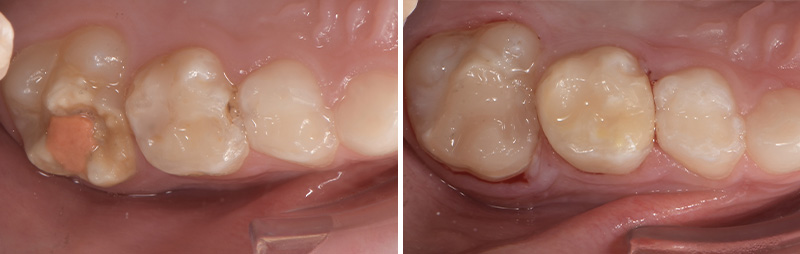

Pour les secteurs postérieurs, en fonction du délabrement tissulaire (PEB ou consécutif à une atteinte carieuse), on optera pour des restaurations directes en composite ou indirectes de type onlay en céramique.

Fig. 06 : traitement postérieur par résine composite.

Fig. 07 : traitement postérieur par onlay céramique.

Même si en pédodontie, pour les restaurations indirectes, le composite est assez plébiscité, le fait de réaliser ces onlays directement en céramique permet non seulement de ne pas réintervenir à l’âge adulte mais également de ne pas avoir d’égression compensatoire ou de perte de DV due à l’usure prématurée du composite. De plus, si des thérapeutiques d’orthodontie doivent être mises en œuvre pendant la croissance, le collage sur de la céramique n’est plus un problème.